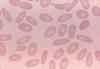

5

Q

A

elliptocytes